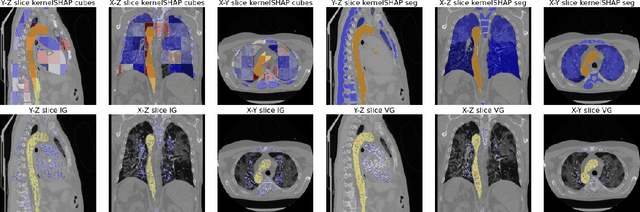

Abstract:Analysis of 3D segmentation models, especially in the context of medical imaging, is often limited to segmentation performance metrics that overlook the crucial aspect of explainability and bias. Currently, effectively explaining these models with saliency maps is challenging due to the high dimensions of input images multiplied by the ever-growing number of segmented class labels. To this end, we introduce Agg^2Exp, a methodology for aggregating fine-grained voxel attributions of the segmentation model's predictions. Unlike classical explanation methods that primarily focus on the local feature attribution, Agg^2Exp enables a more comprehensive global view on the importance of predicted segments in 3D images. Our benchmarking experiments show that gradient-based voxel attributions are more faithful to the model's predictions than perturbation-based explanations. As a concrete use-case, we apply Agg^2Exp to discover knowledge acquired by the Swin UNEt TRansformer model trained on the TotalSegmentator v2 dataset for segmenting anatomical structures in computed tomography medical images. Agg^2Exp facilitates the explanatory analysis of large segmentation models beyond their predictive performance.